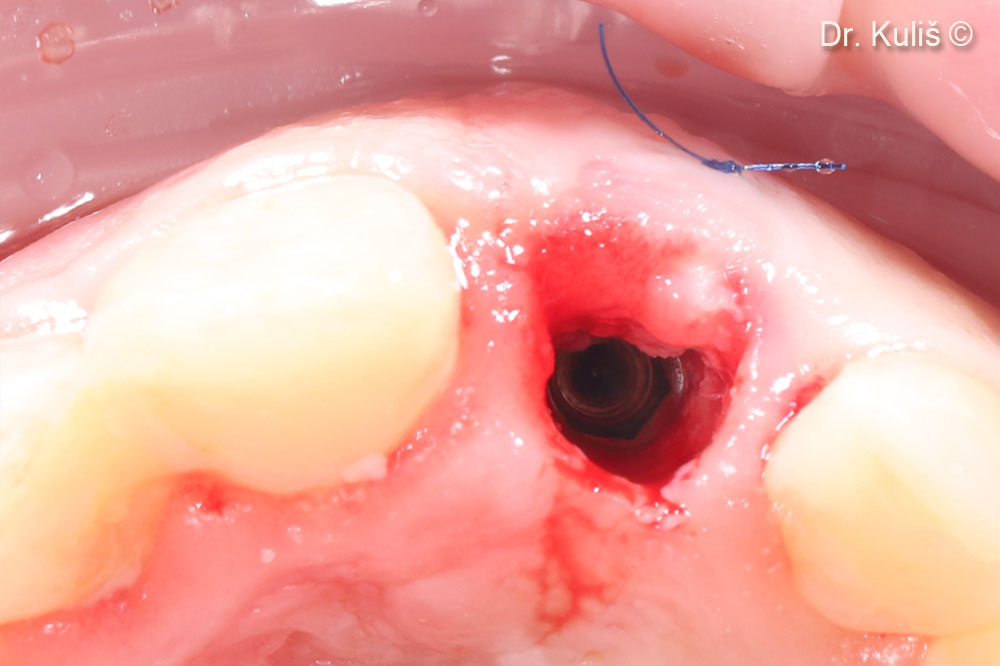

Ca phẫu thuật giai đoạn hai được thực hiện theo phương pháp xâm lấn tối thiểu bằng kỹ thuật vạt cuộn. Hình ảnh cho thấy sự hình thành xương tốt phía trên bệ cấy ghép.

Lộ phần nền tảng cấy ghép